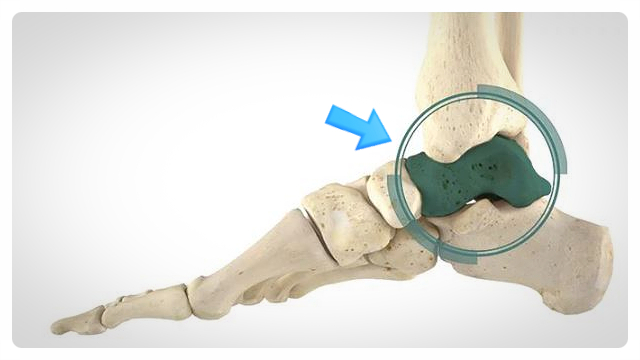

거골(talus)은 발목 부위에 위치한 뼈로, 관절을 형성하는 중요한 축을 담당합니다. 이 부위가 골절되면 인대 손상이나 연골 손상이 동반되는 경우가 많아서, 장기적인 통증과 관절 강직을 유발할 위험성이 높습니다.

일반적인 단순 골절과는 달리 거골 손상 시에는, 관혈적 정복 및 금속 내고정술 같은 졍형외과적 처치가 필요할 수 있는데요. 또한 회복 과정에서도 집중적인 재활운동과 물리치료가 필수입니다.

만약 이러한 의학적 조치가 제대로 이루어지지 않으면, 관절면의 정렬이 어긋나거나 연골 조직의 손상을 초래하는데요. 그렇다면 향후 발목 기능에 심각한 후유증을 남길 수도 있습니다.